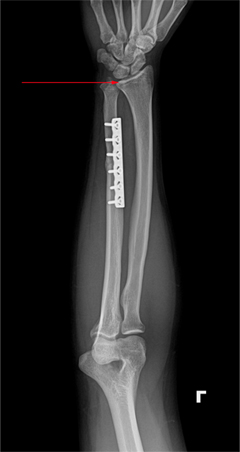

x-ray 사진

교정 수술 후